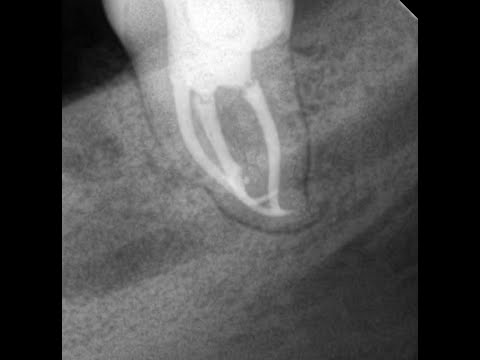

Запись с повторного эндолечения лечения 4.6 dens entomolaris.

Техническое перелечивание зуба 4.6, ранее леченого резорцин-формалиновой пастой. Примечательная анатомия дна полости зуба в связи с наличием дополнительного дистального язычного корня (dens entomolaris). Видео отстаблено, добавлены снимки, подчищен звук от шипений.